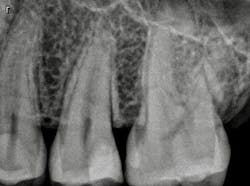

The patient, a 29-year-old man, presented with a failing Class II direct composite restoration in the upper left second premolar (figure 2). A radiograph confirmed the presence of a carious lesion (figure 3). Due to the recurrent caries found in many of the teeth, a conservative treatment plan was made for possible root canal therapy and a direct composite restoration. In cases with recurrent caries, using an RMGI is ideal in that it contains fluoride and provides a more suitable "environment" for restoring deep lesions.

Figure 3: Radiograph confirming carious lesion